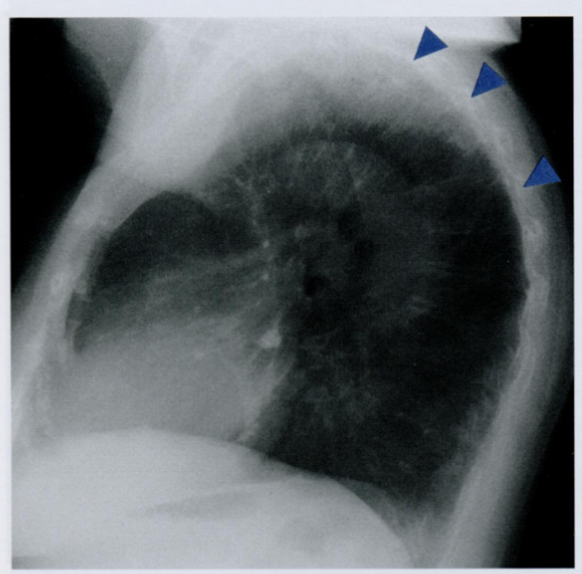

Оцените структуры, отмеченную стрелкой. Как называется данная связка?

Какое заболевание связано с обызвествлением и окостенением данной связки?

На передней поверхности позвоночника часто можно обнаружить обызвествление и окостенение передней продольной связки с участками гиперостоза.

Если эти изменения затрагивают, по меньшей мере, тела четырех позвонков и не связаны с другими дегенеративными изменениями межпозвоночных дисков (остеохондроз, пролапс), как при спондилоартропатиях, то можно ставить диагноз диффузного идиопатического костного гиперостоза, известного также как болезнь Форестье (Forestier-Rotes-Querol).

Заболевание чаще поражает грудопоясничный переход и нижние шейные позвонки.